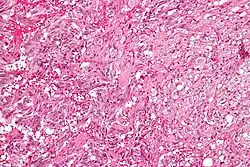

| Micrograph of a gangliocytic paraganglioma. H&E stain. | |

A gangliocytic paraganglioma is a rare tumour that is typically found in the duodenum and consists of three components: (1) ganglion cells, (2) epithelioid cells (paraganglioma-like) and, (3) spindle cells (schwannoma-like).[1]

GP consist of three components (1) ganglion cells, (2) epithelioid cells (neuroendocrine-like), and (3) spindle cells (schwannoma-like). The microscopic differential diagnosis includes poorly differentiated carcinoma, neuroendocrine tumour and paraganglioma.[1]